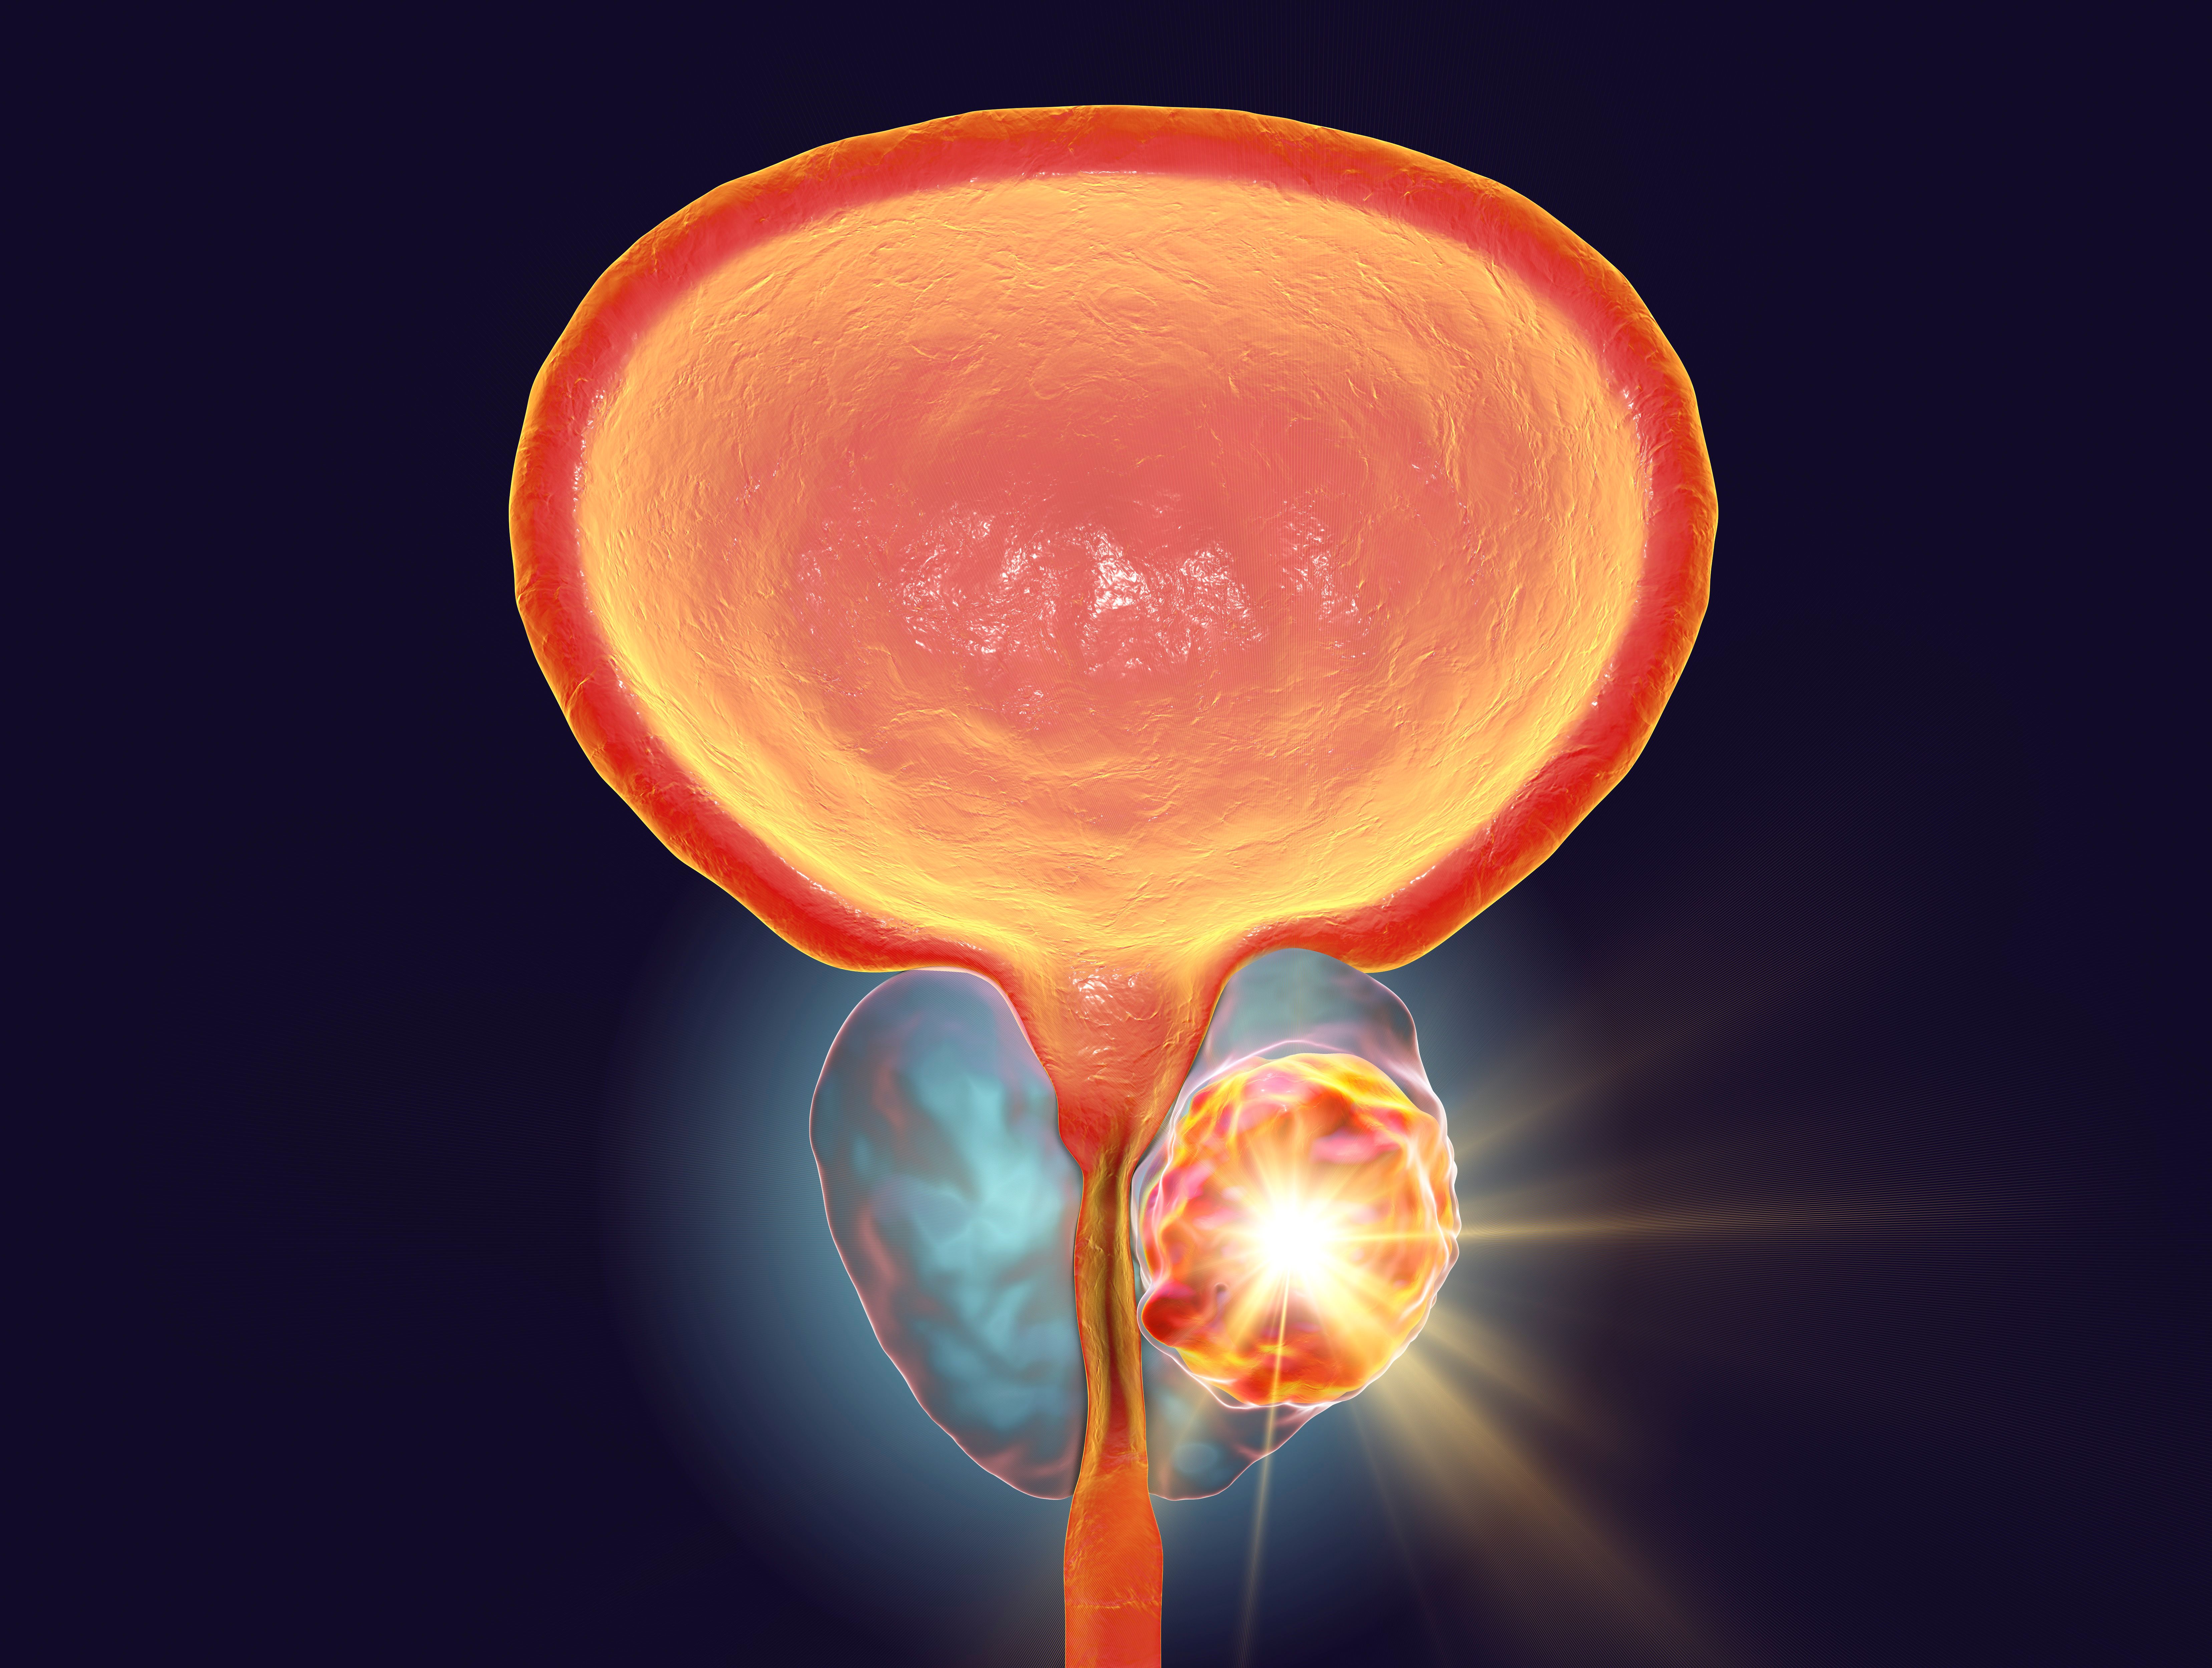

CAN-2409/EBRT Improves Disease-Free Survival in Localized Prostate Cancer

CAN-2409, a localized cytolytic mechanism, administered locally and combined with an oral prodrug significantly enhanced disease-free survival (DFS) outcomes vs placebo when added to standard-of-care (SOC) external beam radiation therapy (EBRT) in patients …